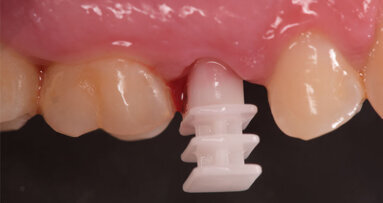

Il poter disporre di una tipologia di fixture estremamente orientata al conseguimento di elevati valori di stabilità primaria ha costituito un ulteriore elemento a favore di questa scelta. La paziente è stata sottoposta ad un trattamento preliminare a cielo coperto mediante levigatura radicolare. Il giorno dell’intervento, sotto profilassi antibiotica, è stata eseguita l’estrazione in maniera micro-traumatica e la rimozione mediante curettage dei tessuti infiammatori presenti. Non è stato eseguito un lembo di accesso, ma è stata verificata la presenza di tessuto osseo in sede vestibolare (Fig. 3).

È stato inserito un impianto Straumann BLX 3.75 mm di diametro per 12 mm di lunghezza, con superficie SLActive seguendo l’asse protesico ideale (Figg. 4, 5). Avendo conseguito una stabilità primaria eccedente i 35 N/cm è stato realizzato un restauro provvisorio avvitato in composito su componente in Titanio da provvisori. Nonostante una sostanziale congruità della forma del provvisorio con la parte superficiale dell’alveolo, è stata utilizzata una matrice dermica suina (Botiss Mucoderm) allo scopo di sigillare il gap presente tra provvisorio e bordo mucoso dell’alveolo. Tale matrice, opportunamente sagomata e forata in modo da essere stabilizzata dal provvisorio stesso, è stata posizionata in modo da non rimanere esposta al cavo orale. Non sono state necessarie suture (Figg. 6-8).

Fig. 3_Alveolo post-estrattivo.

Fig. 6_Matrice dermica suina forata per la stabilizzazione mediante provvisorio.